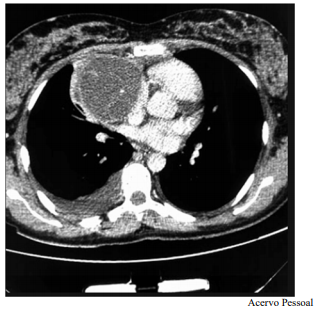

Um paciente de 17 anos de idade revela idas frequentes à emergência por causa de tosse e dispneia. Em exame de imagem investigatório, identificou-se, na tomografia computadorizada de tórax (TCT), uma massa mediastinal anterior bem definida, com densidade de partes moles, medindo cerca de 17 cm x 11 cm x 10 cm, conforme representado na imagem a seguir. A lesão não invadia estruturas adjacentes, e não foram encontradas outras alterações nas tomografias de tórax, de crânio e de abdome. Foi realizada uma biópsia pré-operatória guiada por TCT, cujo diagnóstico foi compatível com teratoma de mediastino.

Considerando esse caso clínico, a imagem apresentada e os conhecimentos médicos correlatos, julgue o item a seguir.